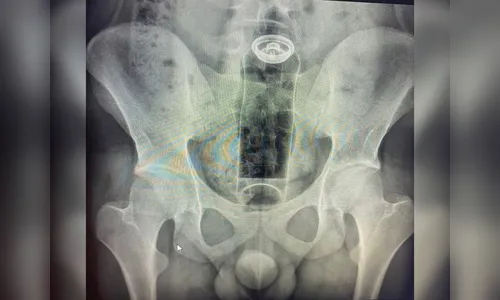

Um rapaz de 19 anos foi levado às pressas ao hospital após um desodorante ficar alojado no ânus durante uma prática sexual. O objeto acabou sendo empurrado para o interior do intestino, o que impossibilitou a retirada por meios caseiros.

Diante da dor intensa e do desconforto abdominal, o jovem buscou atendimento médico. Exames realizados pela equipe de saúde confirmaram a presença do corpo estranho na região retal, sendo necessária uma intervenção especializada para a remoção segura do item.

Após o procedimento, o paciente permaneceu em observação e recebeu alta médica sem registro de complicações graves.

AutorFoto: Reprodução